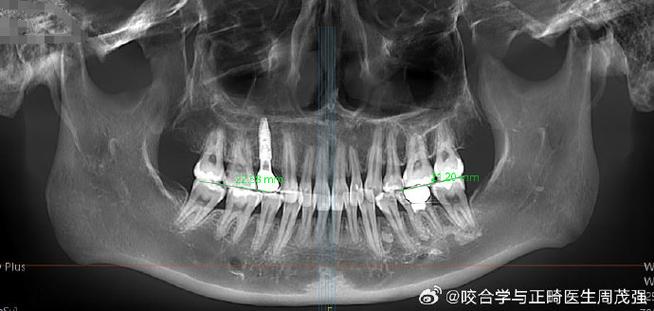

正畸治疗需与口腔颌面外科、关节科医生密切合作,治疗前通过锥形束CT(CBCT)评估髁突吸收程度和下颌骨形态,治疗中定期进行临床检查(关节压痛、开口度)和影像学复查(CBCT或MRI),观察髁突变化,若出现关节疼痛加重、开口受限,需立即暂停矫治,调整方案。

(图片来源网络,侵删) -